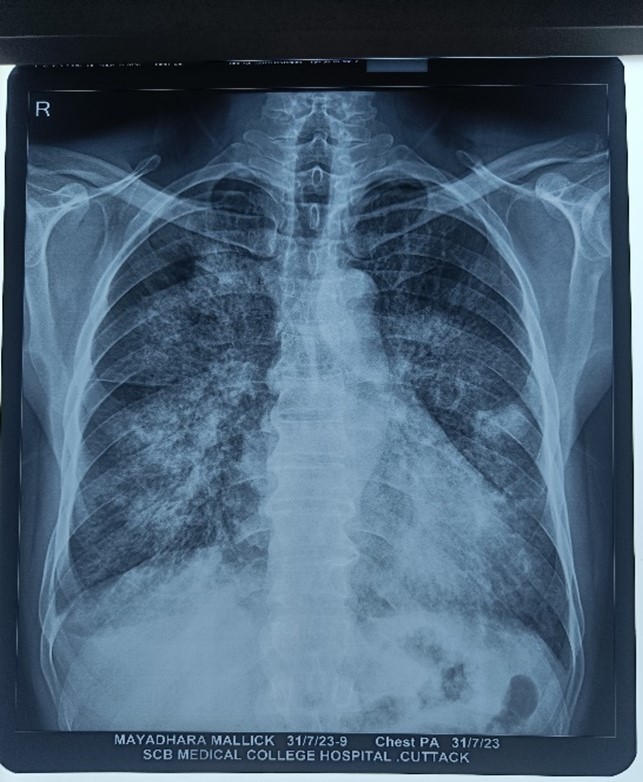

A 42-year-old male known diabetic presented to OPD with complaints of cough with scanty expectoration for 1.5 months (subacute) and shortness of breath for 15 days with a history of fever 1.5 months back subsided but now again high-grade fever for 6 days and chest pain. The patient was admitted to the hospital.

On auscultation, there was b/l coarse crepitations heard, and there was occasional Ronchi as well.

On investigations

- CBC- TLC was raised

- Chest x ray-right upper middle and lower zone haziness and left middle zone haziness

- HRCT-b/l ground glass opacities with bilateral lower lobe and right middle lobe consolidation with atelectasis (Infective aetiology)

- Sputum C/S- klebsiella pneumonia sensitive to tigecycline

A patient was started on tigecycline 50 mg IV BD and other symptomatic treatments. The patient improved clinically and symptomatically after 4 days.